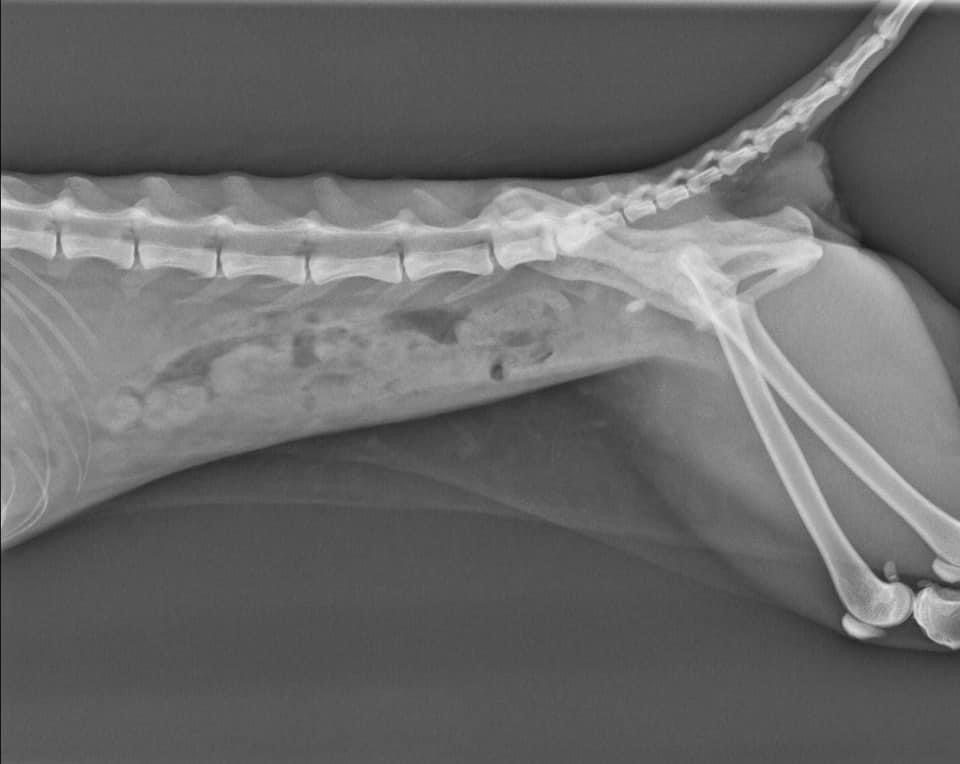

慎重起見。先幫阿咪做個X光檢查。果不其然。找到問題點了。

阿咪膀胱有結石。而導致血尿。但因為阿咪實在太瘦了。體重也只有2.4公斤。

醫生怕立即手術阿咪會對麻醉上有風險。